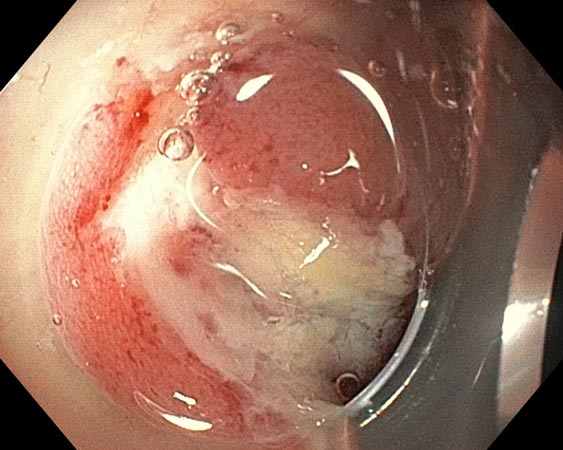

Проводили удаление образования единым блоком для проведения патоморфологического исследования. В случае моноблочной и фрагментарной резекции образования использовали диатермическую петлю SD-210U-25. Сведение краёв клипсами выполняли только после диссекции подслизистых образований (рис. 3–6).

Рис. 3. Частично окаймляющий разрез

Рис. 4. Диссекция в подслизистом слое

Рис. 5. Дефект после удаления

Рис. 6. Клипирование дефекта